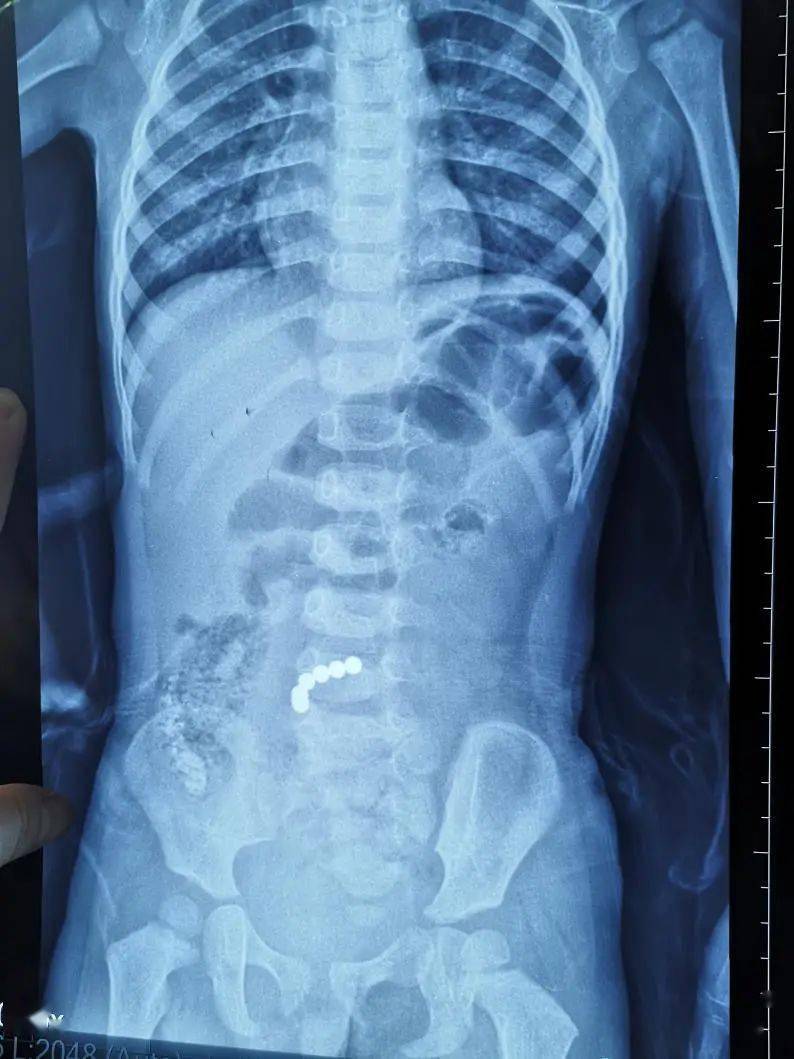

还在给孩子买磁珠模仿光头强男孩吞食11颗磁珠肠穿孔

大学附属第六医院,入住儿科,经腹部平片,ct等相关检查,确诊为小肠异物

误吞药品锡箔包装可怕的结果来了